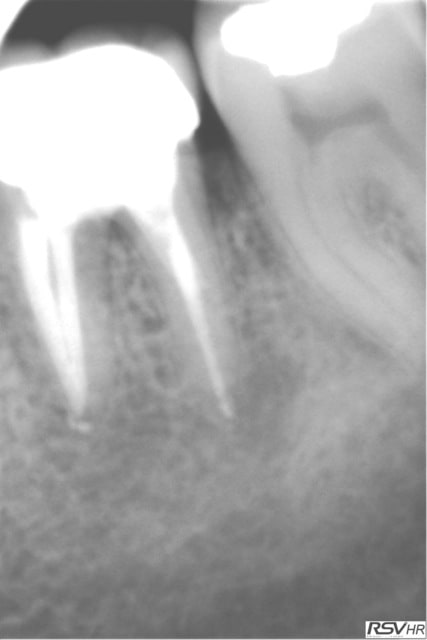

UN exemple de RTE

dépose inlay+couronne en 2009

retraitement sous digue indispensable(même sur dents antérieures la digue ce n'est pas pour faire jolie,c'est pour permettre à l'hypochlorite de rester à demeure tout le long du retraitement;il faut que çà "baigne" pour avoir une chance de

guérison apicale)

ici traitement sous hypo+digue +r-endo;il y a un dépassement léger au périapex

en 2015 guérison apparente du périapex(1h30 de retraitement!)

la dépose de l'inlay avec des ultrasons;désobturation acétate éythyle r-endo gutta compactage mac spadden

5eme photos en2009 et 2010;la dernière en 2015